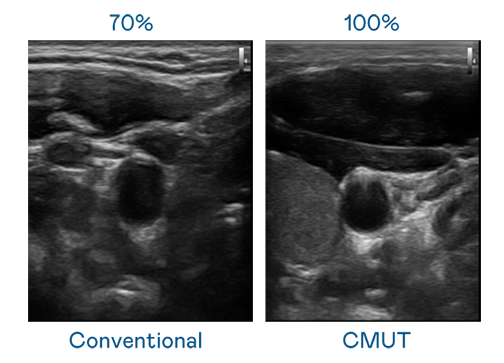

CMUT 技術是一種用電容式微機電元件來產生超音波訊號的技術。與傳統 PZT 壓電式技術相比,CMUT 頻寬增加 30%,更寬頻的超音波訊號讓影像解析度大幅提升,是實現高影像品質醫療超音波掃描、促進精準醫療發展的關鍵技術。

超音波影像的解析度高低,首先取決於探頭能發出的訊號頻寬。CQ9电子 CMUT 可提供高清晰的超音波訊號,提供高頻寬、高靈敏度、影像紋理細節更高的超音波影像,協助醫護人員縮短影像判讀時間及利用精準的醫療影像進行診斷。